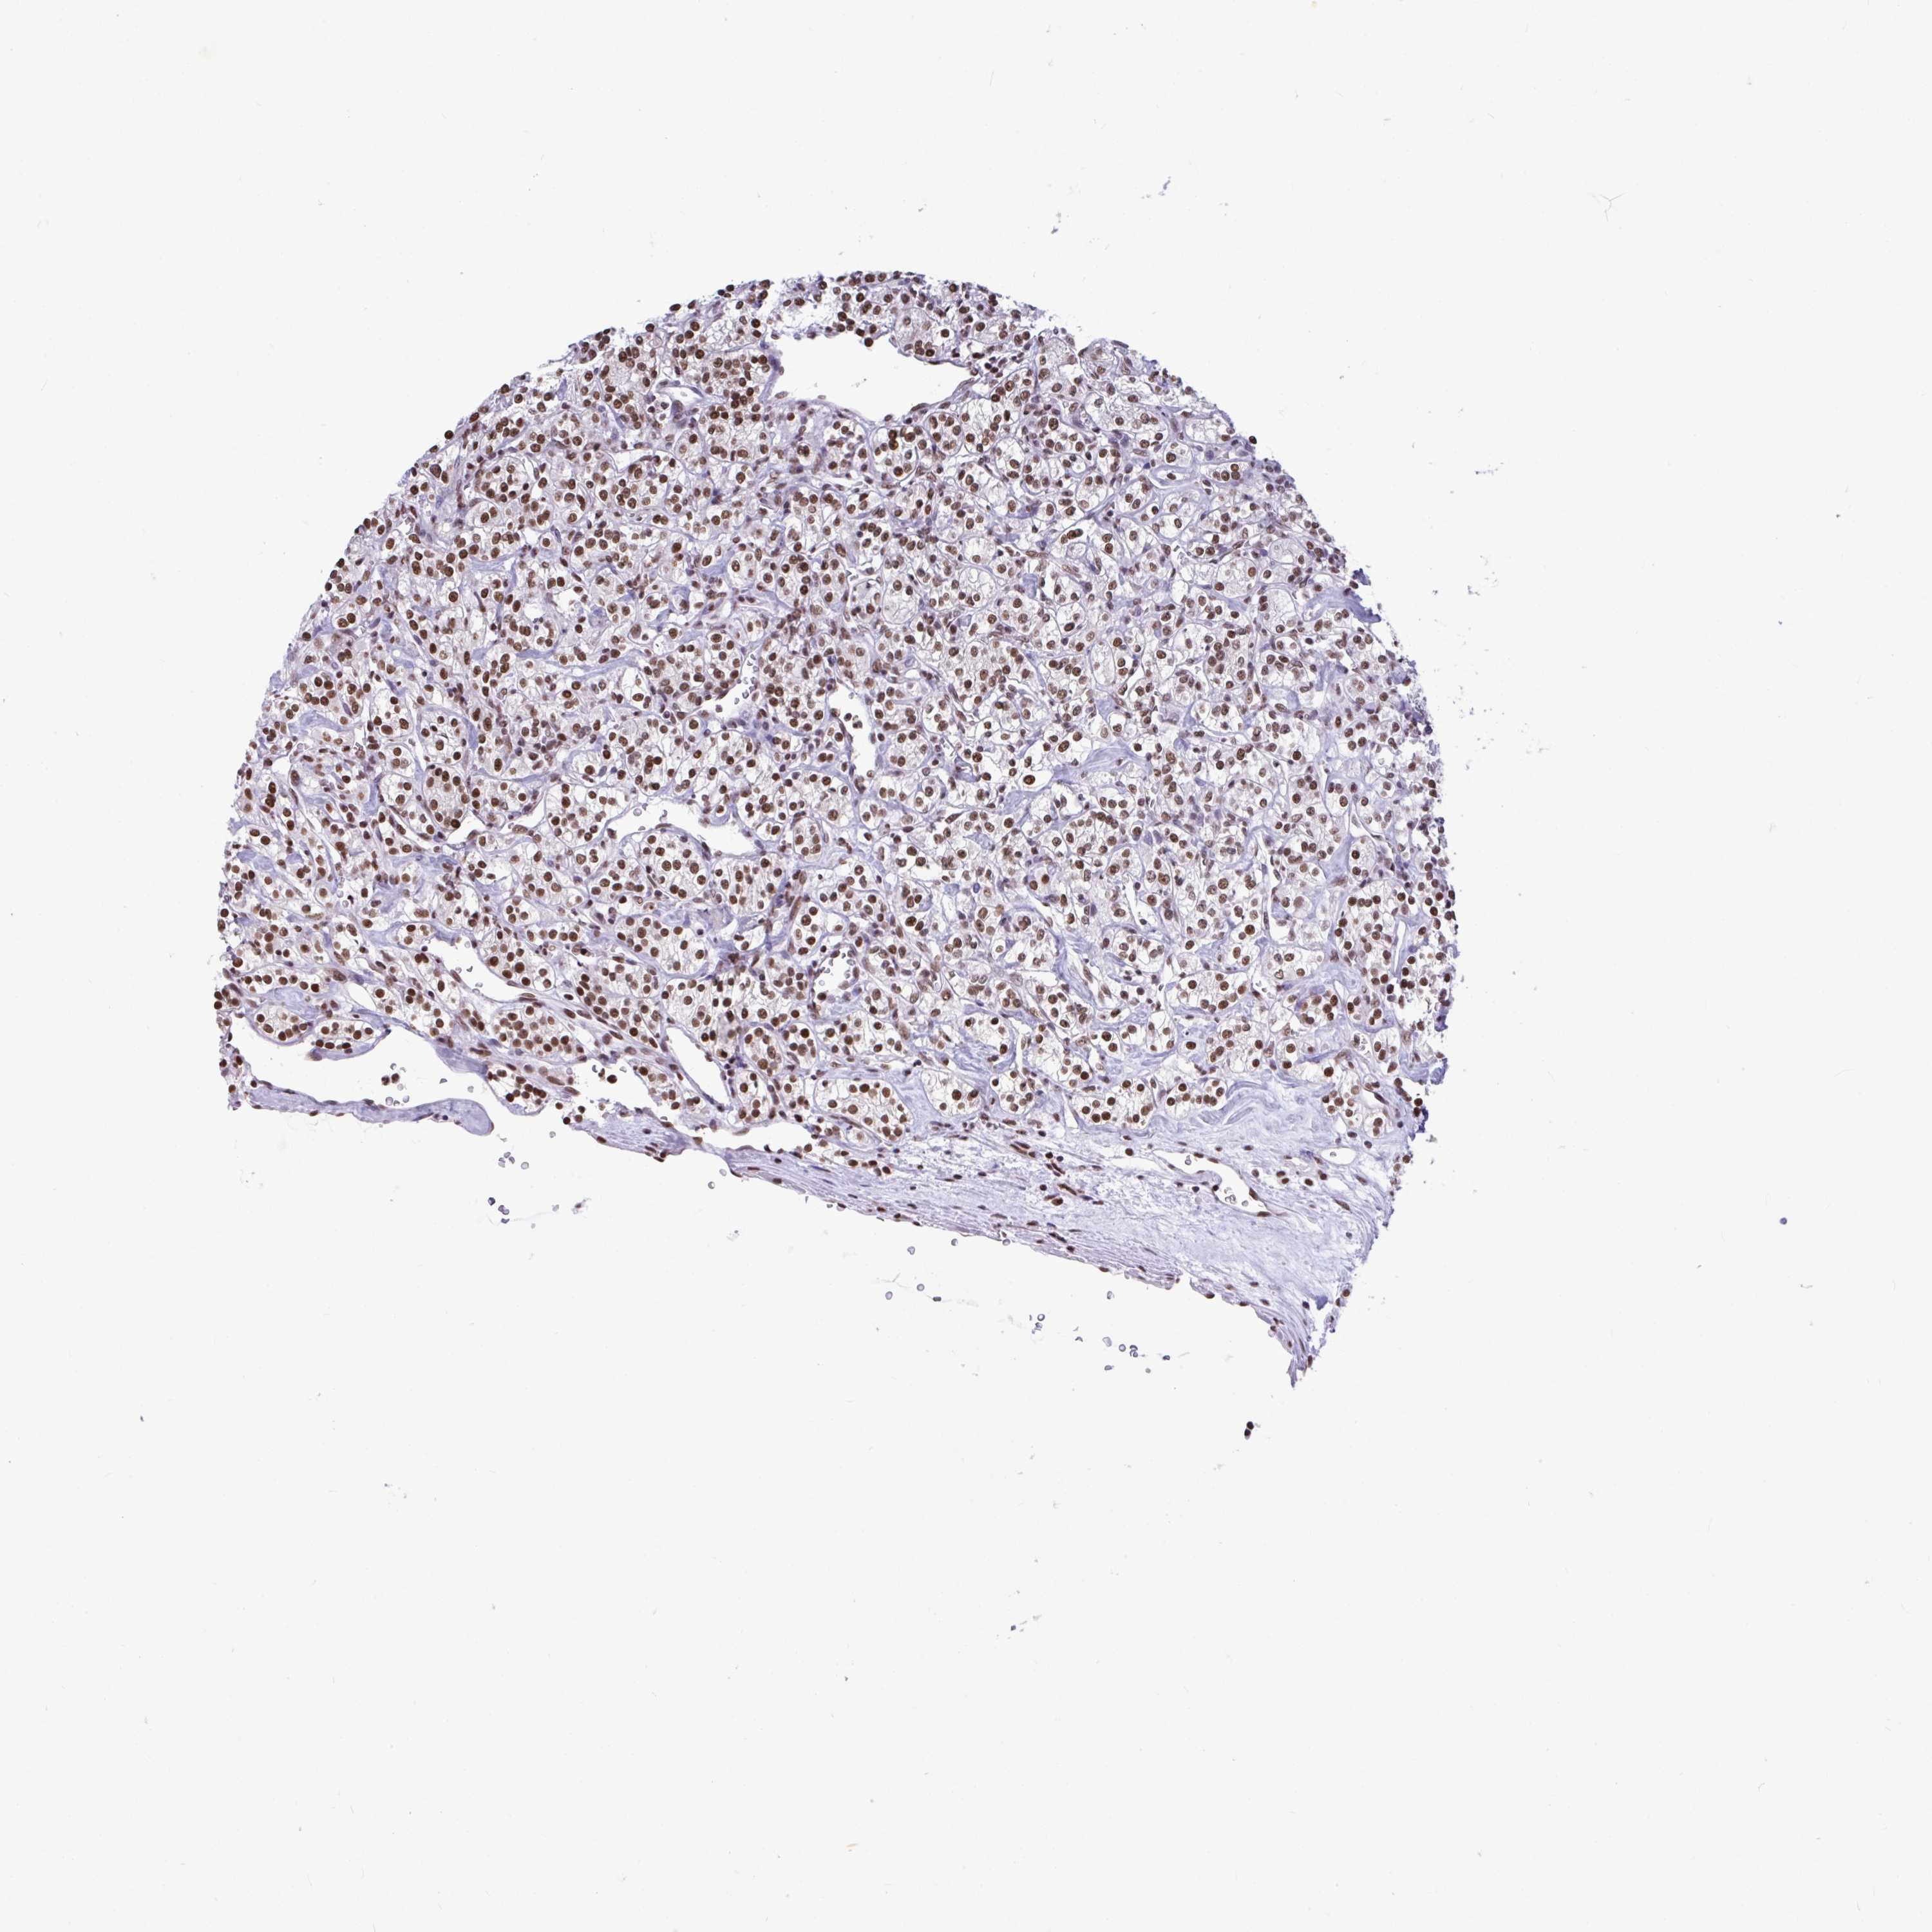

KIDNEY RENAL CLEAR CELL CARCINOMA (VALIDATION) - Interactive survival scatter ploti

The Survival Scatter plot shows the clinical status (i.e. dead or alive) for all individuals in the patient cohort, based on the same data that underlies the corresponding Kaplan-Meier plots. Patients that are alive at last time for follow-up are shown in blue and patients who have died during the study are shown in red.

The x-axis shows the expression levels (FPKM) of the investigated gene in the tumor tissue at the time of diagnosis. The y-axis shows the follow-up time after diagnosis (years). Both axes are complimented with kernel density curves demonstrating the data density over the axes. The top density plot shows the expression levels (FPKM) distribution among dead (red) and alive patients (blue). The right density plot shows the data density of the survived years of dead patients with high and low expression levels respectively, stratified using the cutoff indicated by the vertical dashed line through the Survival Scatter plot. This cutoff is automatically defined based on the FPKM cutoff that minimizes the p-score. The cutoff can be changed by dragging the vertical line or by entering a cutoff value in the square labeled "Current cut-off".

Under the Survival Scatter plot the p-score landscape (black curve; left axis) is shown together with dead median separation (red curve; right axis). Dead median separation is the difference in median mRNA expression between patients who have died with high and low expression, respectively. It is calculated as follows: median FPKM expression of dead patients with high expression - median FPKM expression of dead patients with low expression. This is intended to aid the user in visually exploring custom cutoffs and the associated p-scores and dead median separation.

Individual patient data is displayed and can be filtered by clicking on one or more of the category buttons on the top of the page. Categories describing expression level and patient information include: high, low, alive, dead, female, male and tumor stages. The scale of the x-axis can be toggled between linear and log-scale by clicking on the "x log" button. Mouse-over function shows TCGA ID, patient information and mRNA expression (FPKM) for each patient.

& Survival analysisi

Kaplan-Meier plots summarize results from analysis of correlation between mRNA expression level and patient survival. Patients were divided based on level of expression into one of the two groups "low" (under cut off) or "high" (over cut off). X-axis shows time for survival (years) and y-axis shows the probability of survival, where 1.0 corresponds to 100 percent.

HNRNPDL is not prognostic in Kidney Renal Clear Cell Carcinoma (validation)

Best expression cut offi

Based on the FPKM value of each gene, patients were classified into two groups and association between prognosis (survival) and gene expression (FPKM) was examined. The best expression cut-off refers the FPKM value that yields maximal difference with regard to survival between the two groups at the lowest log-rank P-value. Best expression cut-off was selected based on survival analysis .

When clicking on this number, the vertical dashed line indicating cut-off, the interactive survival plot, and the Kaplan-Meier curve will be adjusted to show results based on the best expression cut-off.

: 236.33

Median expressioni

Median expression refers to the median FPKM value calculated based on the gene expression (FPKM) data from all patients in this dataset. When clicking on this number, the vertical dashed line indicating cut-off, the interactive survival plot, and the Kaplan-Meier curve will be adjusted to show results based on the median expression.

: N/A

Median follow up timei

Median follow up time refers to the median time (years) after diagnosis with this type of cancer, based on clinical data from all patients in this dataset.

P scorei

Log-rank P value for Kaplan-Meier plot showing results from analysis of correlation between mRNA expression level and patient survival.

N/A

5-year survival highi

5-year survival for patients with higher expression than the expression cutoff.

For melanoma and glioma, 3-year survival is shown.

5-year survival lowi

5-year survival for patients with lower expression than the expression cutoff.

TCGA RNA samplesi

RNA-seq data is reported as average FPKM (number Fragments Per Kilobase of exon per Million reads), generated by the The Cancer Genome Atlas (TCGA) .

Normal distribution across the dataset is visualized with box plots, shown as median and 25th and 75th percentiles. Points are displayed as outliers if they are above or below 1.5 times the interquartile range. FPKM values of the individual samples are presented next to the box plot.

Average pTPM 209.4

Number of samples 100